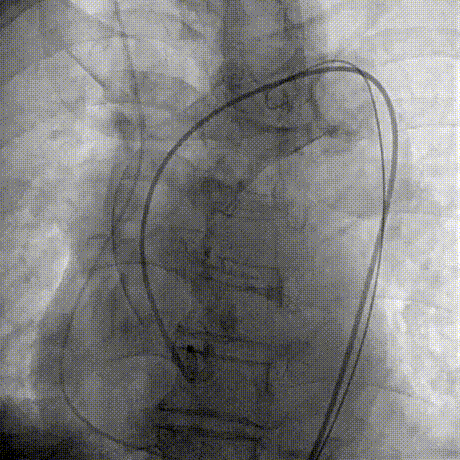

Step 1.升主动脉情况评估

Step 2.建立大鞘通路:大鞘通过升主、边进入边加弯,避免剐蹭弓部斑块

过弓示意图